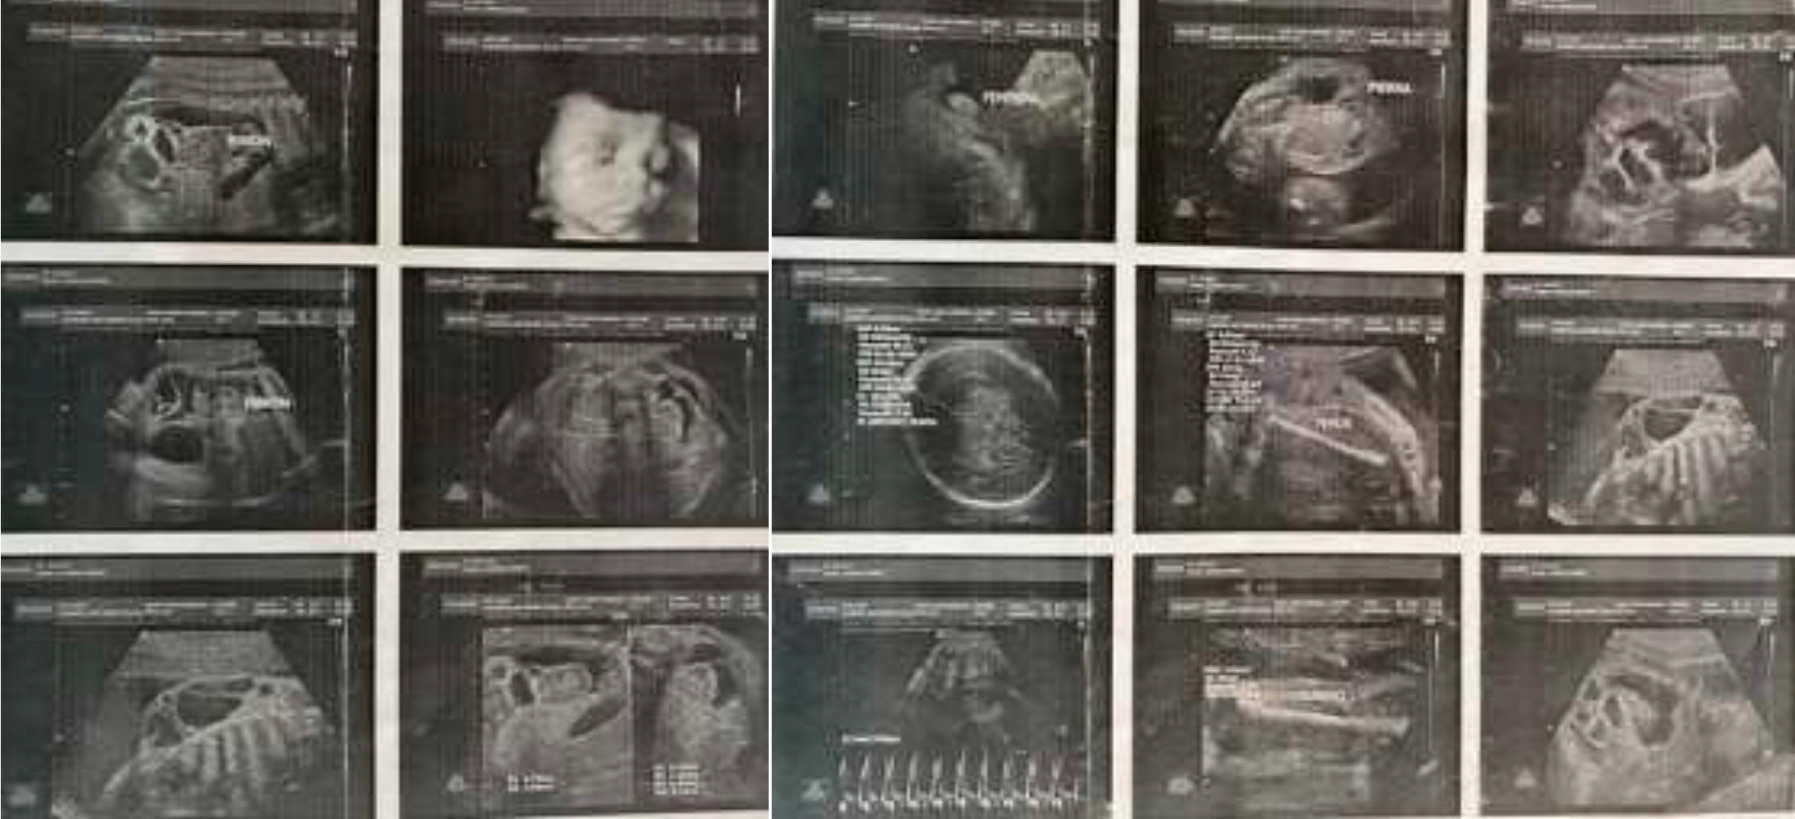

Síndrome de bandas amnióticas: reporte de caso y revisión de literatura

Yolima Alfaro, Luis Fernando Rodríguez, María Mercedes Domínguez, Luis Fernando Molineros Gallón, Ana Ximena Pintae, José Dario Portillo-Miño

14-17